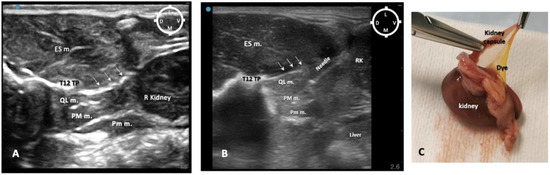

3.3. Computed Tomography Study

Based on the CT images, the injection site occurred between T12 and L1 vertebrae, particularly at L1 (16/20), and at the level of T12-L1 (4/20).

According to the CT study, the distribution of the injectate was considered adequate when the injectate covered the cranial mesenteric ganglion, the celiac ganglion and sympathetic trunk from T10 to L3 vertebrae without further caudal or cranial distribution. The adequacy of the injectate spread to achieve a sympathetic trunk block evaluated by the CT study revealed that this was successfully achieved in 0/5 (0%) of the hemi-rabbits in the 0.1 mL/kg group; 0/5 (0%) of the hemi-rabbits in the 0.2 mL/kg group; 5/5 (100%) of the hemi-rabbits in the 0.3 mL/kg group; and 0/5 (0%) of the hemi-rabbits in the 0.4 mL/kg group. The spread of the contrast was not sufficient to cover the target area in rabbits in the 0.1 and 0.2 mL/kg groups, and a spread caudal to L3 occurred in rabbits in the 0.4 mL/kg group.

Overall, CT images showed that zero (0)/20 injections were in unwanted locations such as the abdominal cavities, surrounding organs, epidural canal or other muscle structures (Figure 7A–C).

Figure 7. Computed tomography (CT) multiplanar study in a rabbit cadaver in which ultrasound-guided quadratus lumborum block was performed using a dorsal approach and medial injection of a volume of 0.2 mL/kg on the left side (L) and 0.3 mL/kg on the right side (R) of a mixture of lidocaine 2%, permanent yellow tissue dye, and iodine contrast (3:1:1). Injection point L1 bilaterally. (A) Sagittal multiplanar reconstruction image showing the distribution of the injectate (yellow asterisks) from eleventh thoracic vertebrae (T11) to intervertebral space between lumbar vertebrae L2-L3 (R side). (B) Transverse multiplanar reconstruction image showing the contrast distribution (yellow asterisk) at the level of caudal T-12 on both R and L sides with medial distribution, location of the sympathetic trunk, more pronounced in the R side comparing to the L side. (C) Three-dimensional reconstruction of the CT image of the same rabbit showing a linear pattern of distribution of the mixture on the R, and L hemi thoraco-lumbar area after QLBs. Cd caudal; Cr cranial; D dorsal; ESM erector spinae muscles; QL quadratus lumborum muscle; V ventral.